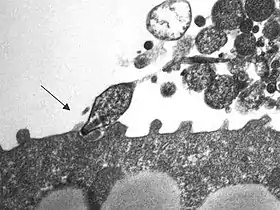

Mycoplasma pneumoniae é uma das menores bactérias conhecidas pelo ser humano. É causadora da pneumonia por Mycoplasma, um tipo de pneumonia bacteriana. Este microorganismo pode apenas sobreviver como parasita em outras células.[1]

Este tipo de bactéria não possui parede celular de glicopeptídeos, como todas as outras da classe Mollicutes. Como alternativa, possui uma membrana celular de esterol, da mesma forma que as células eucarióticas. O esterol é obtido a partir de substâncias do hospedeiro, acumuladas em simples estruturas. Como não tem parede celular, estes organismos são resistentes aos efeitos da penicilina e outros antibióticos beta-lactâmicos que atuam destruindo a parede celular bacteriana.